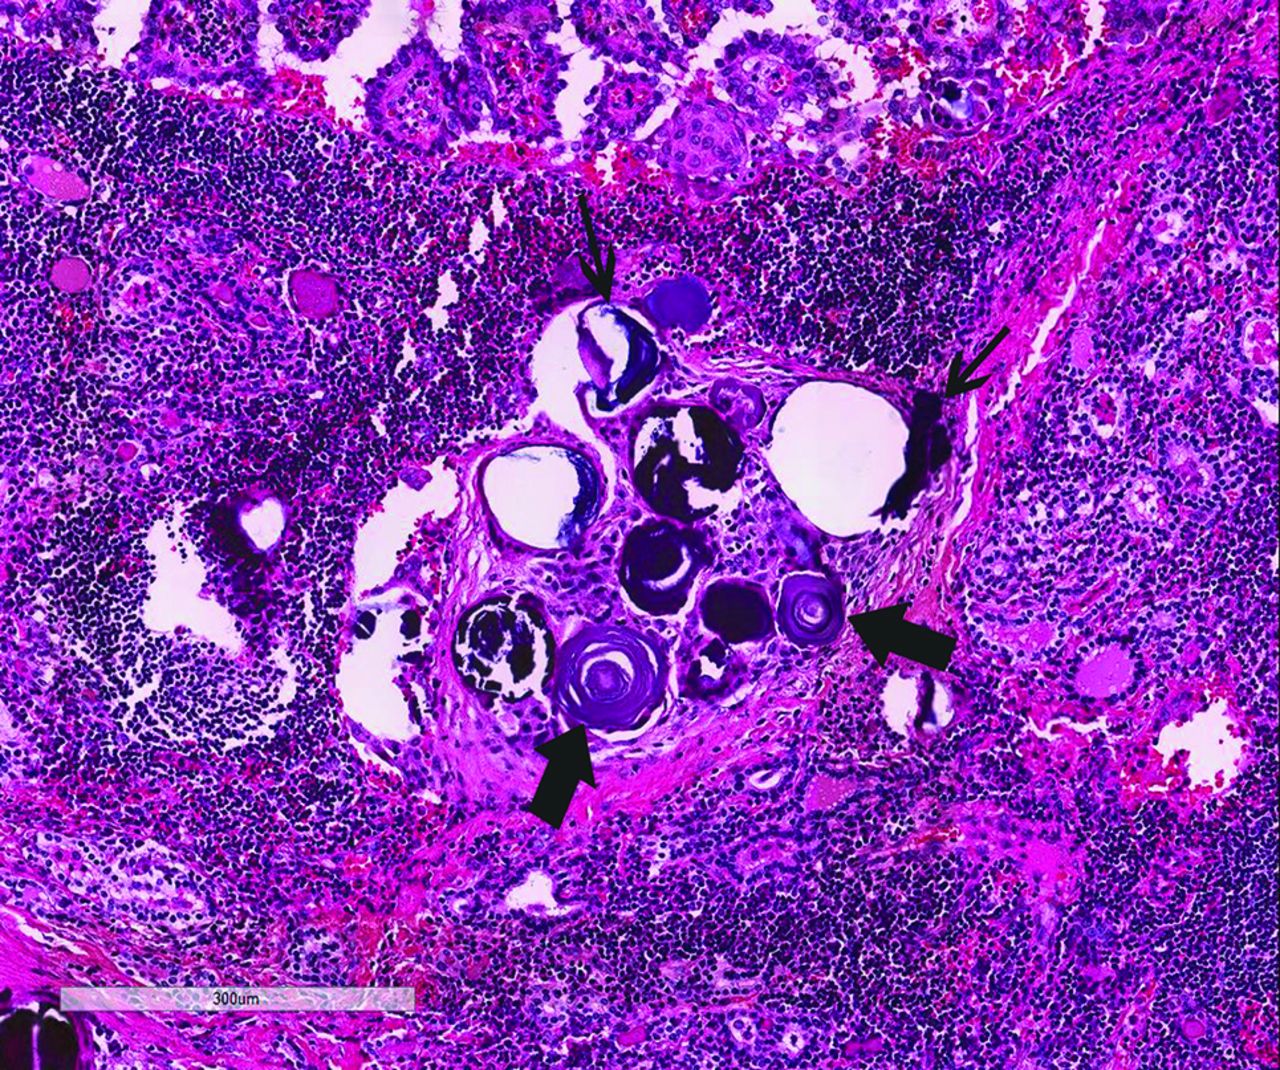

The Bethesda System for Reporting Thyroid Cytopathology was used to classify the thyroid nodules as follows: nondiagnostic, benign, atypia or follicular lesion of undetermined significance, follicular neoplasm/suspicious for follicular neoplasm, suspicious for malignancy, or malignant.14 Surgical pathology slides of the thyroidectomy specimens were retrospectively reviewed by the same pathologist. Care was taken to ensure that each surgical pathology sample corresponded in size and location to the designated nodule noted on the US evaluation. Histology samples were evaluated for the presence of psammomatous and stromal calcifications based on the previous descriptions in the literature, with a typical example demonstrated in Fig 2.6 The distribution of each type of calcification was characterized as sparse, focal, or diffuse. Sparse was defined as rare calcifications that were detected only on close screening; focal, as calcifications easily identified but localized to 1 area; and diffuse, as calcifications scattered throughout the tumor, as described by Tahvildari et al.7 Colloid, if present, was characterized as thin versus “sticky.”5

Examples of psammomatous (thick arrows) and stromal calcifications (thin arrows) from a thyroidectomy specimen of a 16-year-old girl showing papillary thyroid carcinoma in a background of lymphocytic thyroiditis (hematoxylin-eosin stain, 20×).